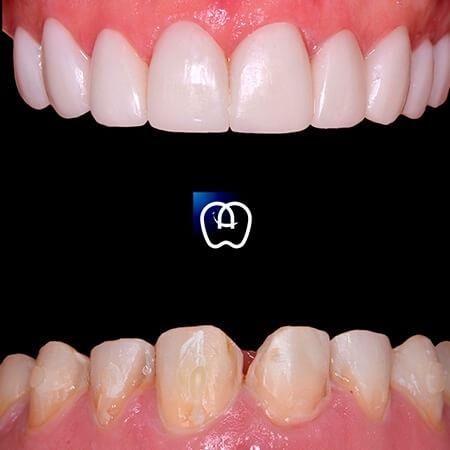

Galería de antes y después